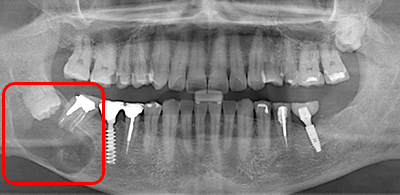

症例Case

親知らず、場合によってはこんなことも

放置していた親知らずの為に、手前の歯と顎の中に病気が発生し、2本の歯を抜歯せざるをえなくなりました。

顎の病気が大きすぎたため、顎の切断をしなければならなくなる一歩手前でした。

このような病状になる前に、早期の親知らず抜歯を推奨しております。